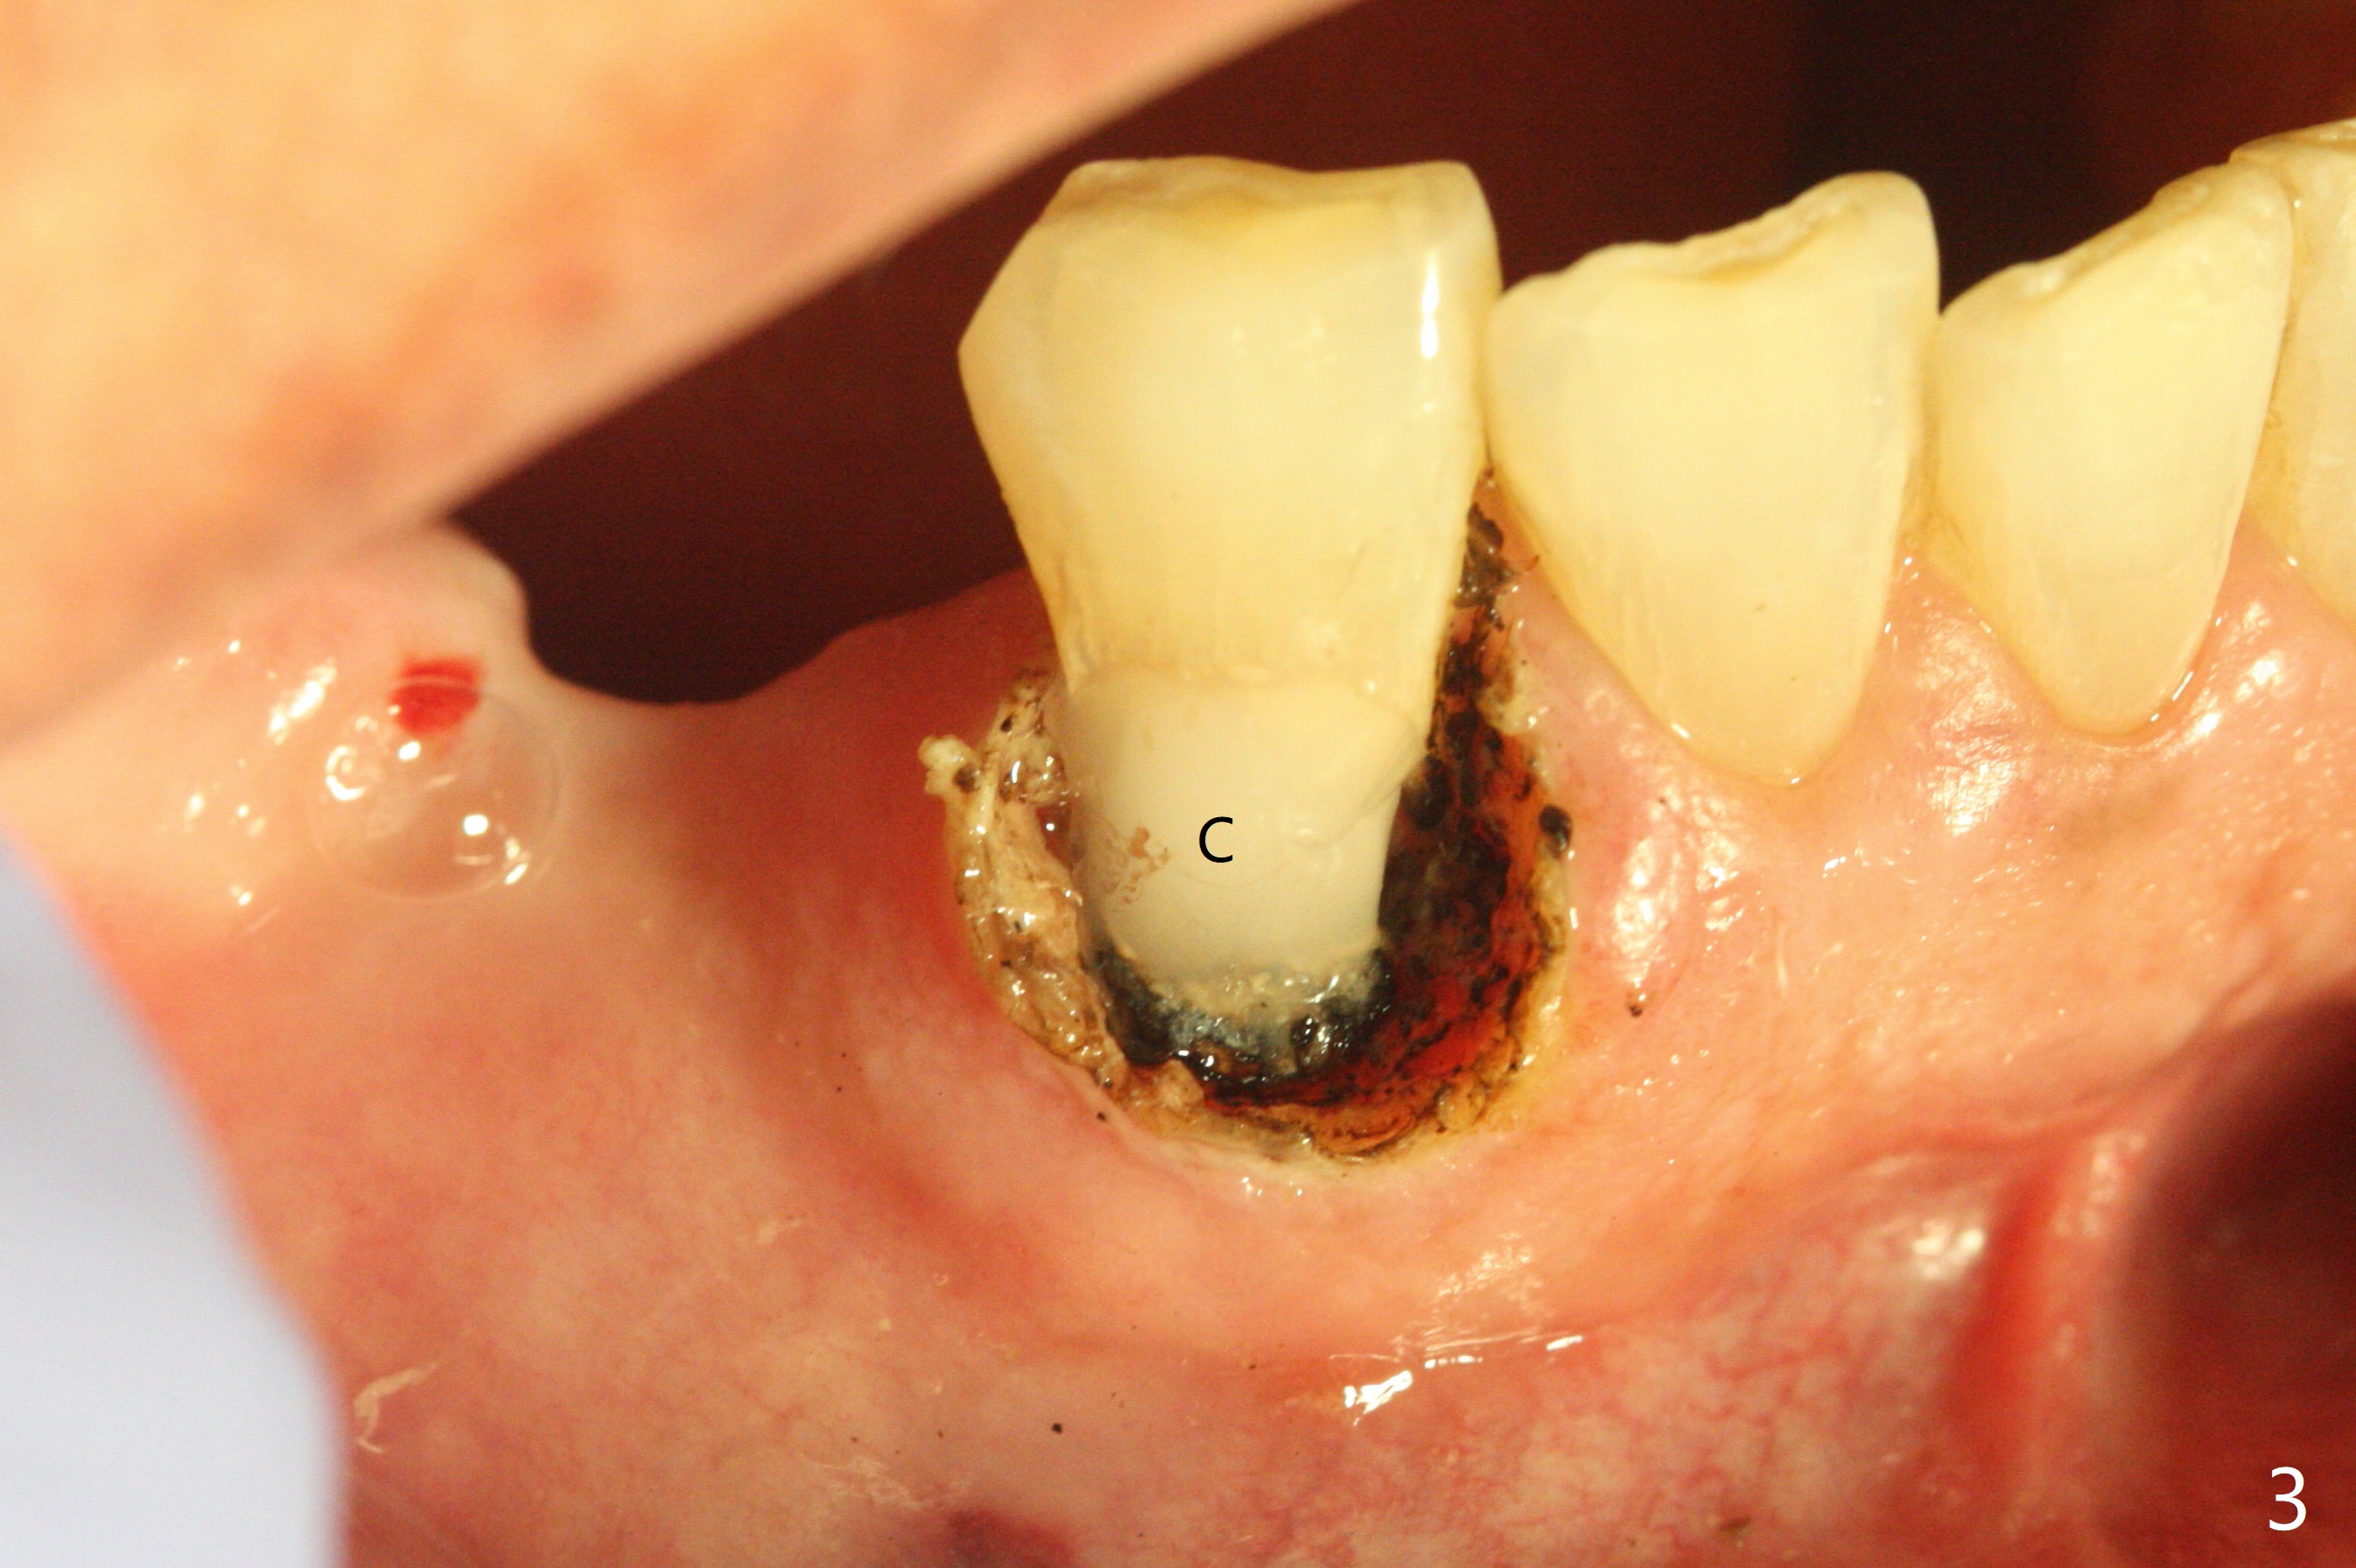

A 63-year-old man requests repair of Class V caries at #27 (Fig.1,2 *). With local anesthesia, Diode laser is used for gingivectomy for composite (Fig.3 C).